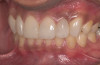

Figure 2  Supraeruption of a lower incisor due to wear on the palatal of the upper anterior.

Figure 2